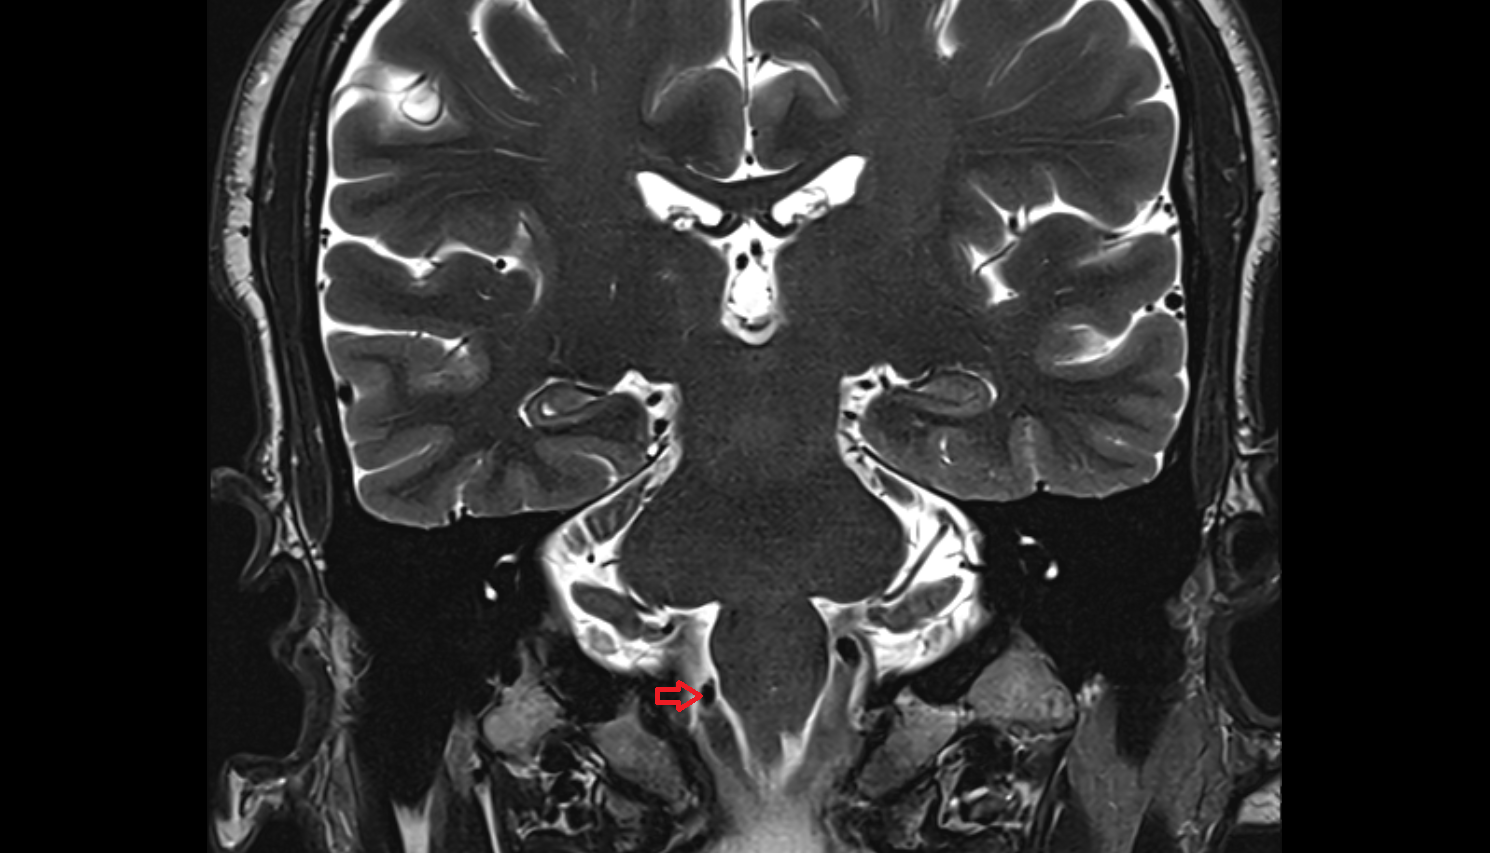

- Spinal cord

- Upper cervical spinal cord

- Cisterna magna

- Premedullary cistern